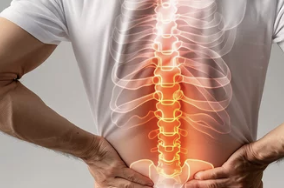

등 통증이 의심되는 병 – 단순한 근육통이 아닐 수도 있는 9가지 질환

하지만 지속적이거나 특정 부위가 찌르듯 아픈 등 통증은

단순 근육통을 넘어 심장, 폐, 췌장, 척추, 신장 등 내장기관 이상이나 신경계 질환의 신호일 수도 있습니다.